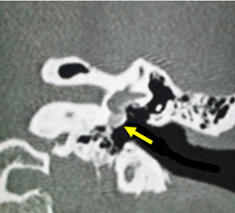

Se solicitó tomografía de cráneo simple la cual evidenció ocupación del seno frontal, maxilar izquierdo y etmoidal anterior. En región frontal se observó edema con una colección y presencia de gas, además de dehiscencia de la tabla anterior del seno frontal. Reconstrucción tridimensional tomográfica 1; momento de la tomografía, no se evidenciaron datos de compromiso intracraneal por imagen.

f1.png  f2.png  f3.png

Tomografía tridimensional 1perforacion tabla externa del seno frontal  Figura 1. Tomografía contrastada con ocupación de los senos frontal y etmoidal, además de formación de absceso en región frontal. Figura 2. Tomografía computarizada con opacificación de seno maxilar izquierdo y etmoidal izquierdo anterior.